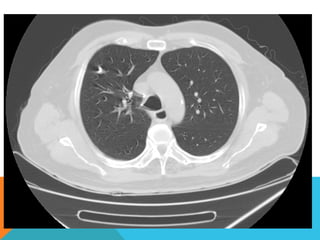

ABORDAJE TÉCNICO: Serealiza estudio con ventana mediastinal y de parénquima pulmonar con técnica de ALTA RESOLUCION, en inspiración y espiración, mediante  cortes axiales, desde ápices hasta bases pulmonares, con las siguientes observaciones En las partes blandas y las estructuras óseas dentro de los límites de la normalidad. Las regiones axilares libres. Ambos pulmones con neumatización conservada, con sobredistensión pulmonar, y áreas de atrapamiento aéreo, bilateral con cambios fibrosos cicatriciales apicales derechos. Se demuestran áreas de condensación en topografía predominantemente parenquimatosa pulmonar derecha, la mayor de ellas evidenciada hacia la base, acompañada de broncograma aéreo, la medición máxima al corte axial de 6.1 por 2.2 cm, en topografía del segmento posterior del lóbulo inferior, S10 así como también otra más se definen topografía de similares características en topografía del segmento medial del lóbulo medio, S5. En topografía parenquimatosa pulmonar izquierda imagen de similares características a las ya descritas en topografía del segmento lingular inferior, S4. No hay derrame ni áreas de engrosamiento pleurales. El patrón vascular es de características normales donde no se delimitan imágenes de lesiones aneurismáticas únicamente cambios por aortoesclerosis incipiente. El corazón de dimensiones conservada, de contornos regulares, sin desplazamientos; en la región hiliar derecha se define adenopatía de medición máxima corte axial de 1.6 por 1.4 cm.

En los cortesrealizados hacia las bases pulmonares es posible delimitar los órganos sólidos intraabdominales tales como el hígado sin anormalidades que consignar; se demuestra imagen hiperdensa puntiforme en topografía del parénquima esplénico en relación a calcificación inespecífica. Hay distensión aérea esofágica que lo define prácticamente su totalidad. Se demuestran imágenes hiperdensas en topografía intraluminal vesicular que corresponden con colelitiasis. Se define imagen hipodensa parenquimatosa renal superior derecha con patrón de atenuación homogéneo, líquido que condiciona la sospecha de lesión focal benigna tipo quística simple. INTERPRETACIÓN DIAGNÓSTICA:   ESTUDIO ANORMAL QUE DEMUESTRA HALLAZGO INESPECIFICO DE SOBREDISTENSIÓN PULMONAR  CON CAMBIOS FIBROSOS CICATRICIALES APICALES DERECHOS Y ÁREAS DE CONDENSACIÓN PARENQUIMATOSAS PULMONARES, DE PREDOMINIO DERECHO, LA DE MAYORES DIMENSIONES BASAL DERECHA, ASOCIADA CON BRONCOGRAMA AÉREO. COLELITIASIS.

El estudio radiológicosimple evidencia una lesión nodular menor del centímetro, radiodensa, caracterizada como granuloma cálcico. En mi opinión el estudio de TCAR fue realizado por ese motivo y ello permito identificar los hallazgos “floridos” que ya se señalan y se muestran en las imagen axiales ya seleccionadas.